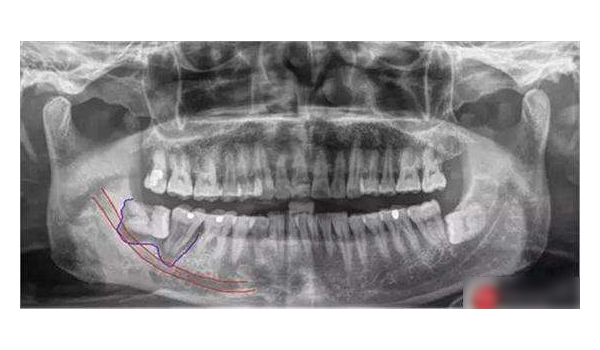

汕頭日?qǐng)?bào) | 恒牙“跑偏”長在牙根中間 醫(yī)生巧手為患者拔除2024-08